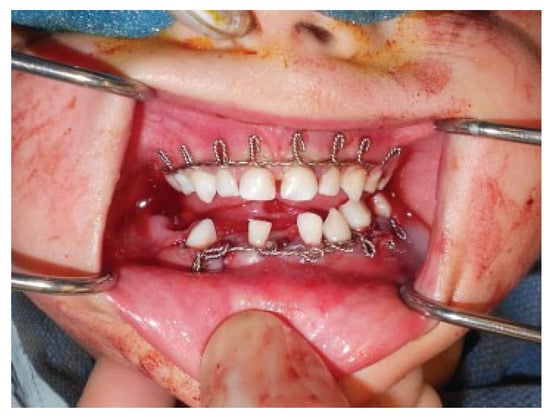

Modifications to this procedure include using 24-gauge stainless steel wire that is passed from the last molar as originally described (Figure 2). The wire is then twisted from one side of the dental arch to the other (Figure 3). Ideally, circumdental ligatures are passed to secure the individual teeth as the cable is being twisted (Figure 4). This will allow for secure fastening of the cable and ligature complex. Finally, when the wires composing the Risdon cable have reached the contralateral molar tooth, it is then secured and the final circumdental ligature is placed. The circumdental wires are cut and twisted in a traditional fashion that will allow loops for securing elastics or wiring to establish MMF or guiding functions (Figure 5). If elastics are used for MMF, it is most unusual for the Risdon wiring to pull off or otherwise fail as the elastics “give.” Aside from establishing MMF, this procedure may also be used for splinting avulsed or luxated teeth, and may be supplemented with autopolymerizing resin for stability (Figure 6). Following application of the Risdon cable, open reduction internal fixation may then be performed with the patient in MMF (Figure 7).

Figure 4. Interdental wiring for stabilization of cable and individual teeth.